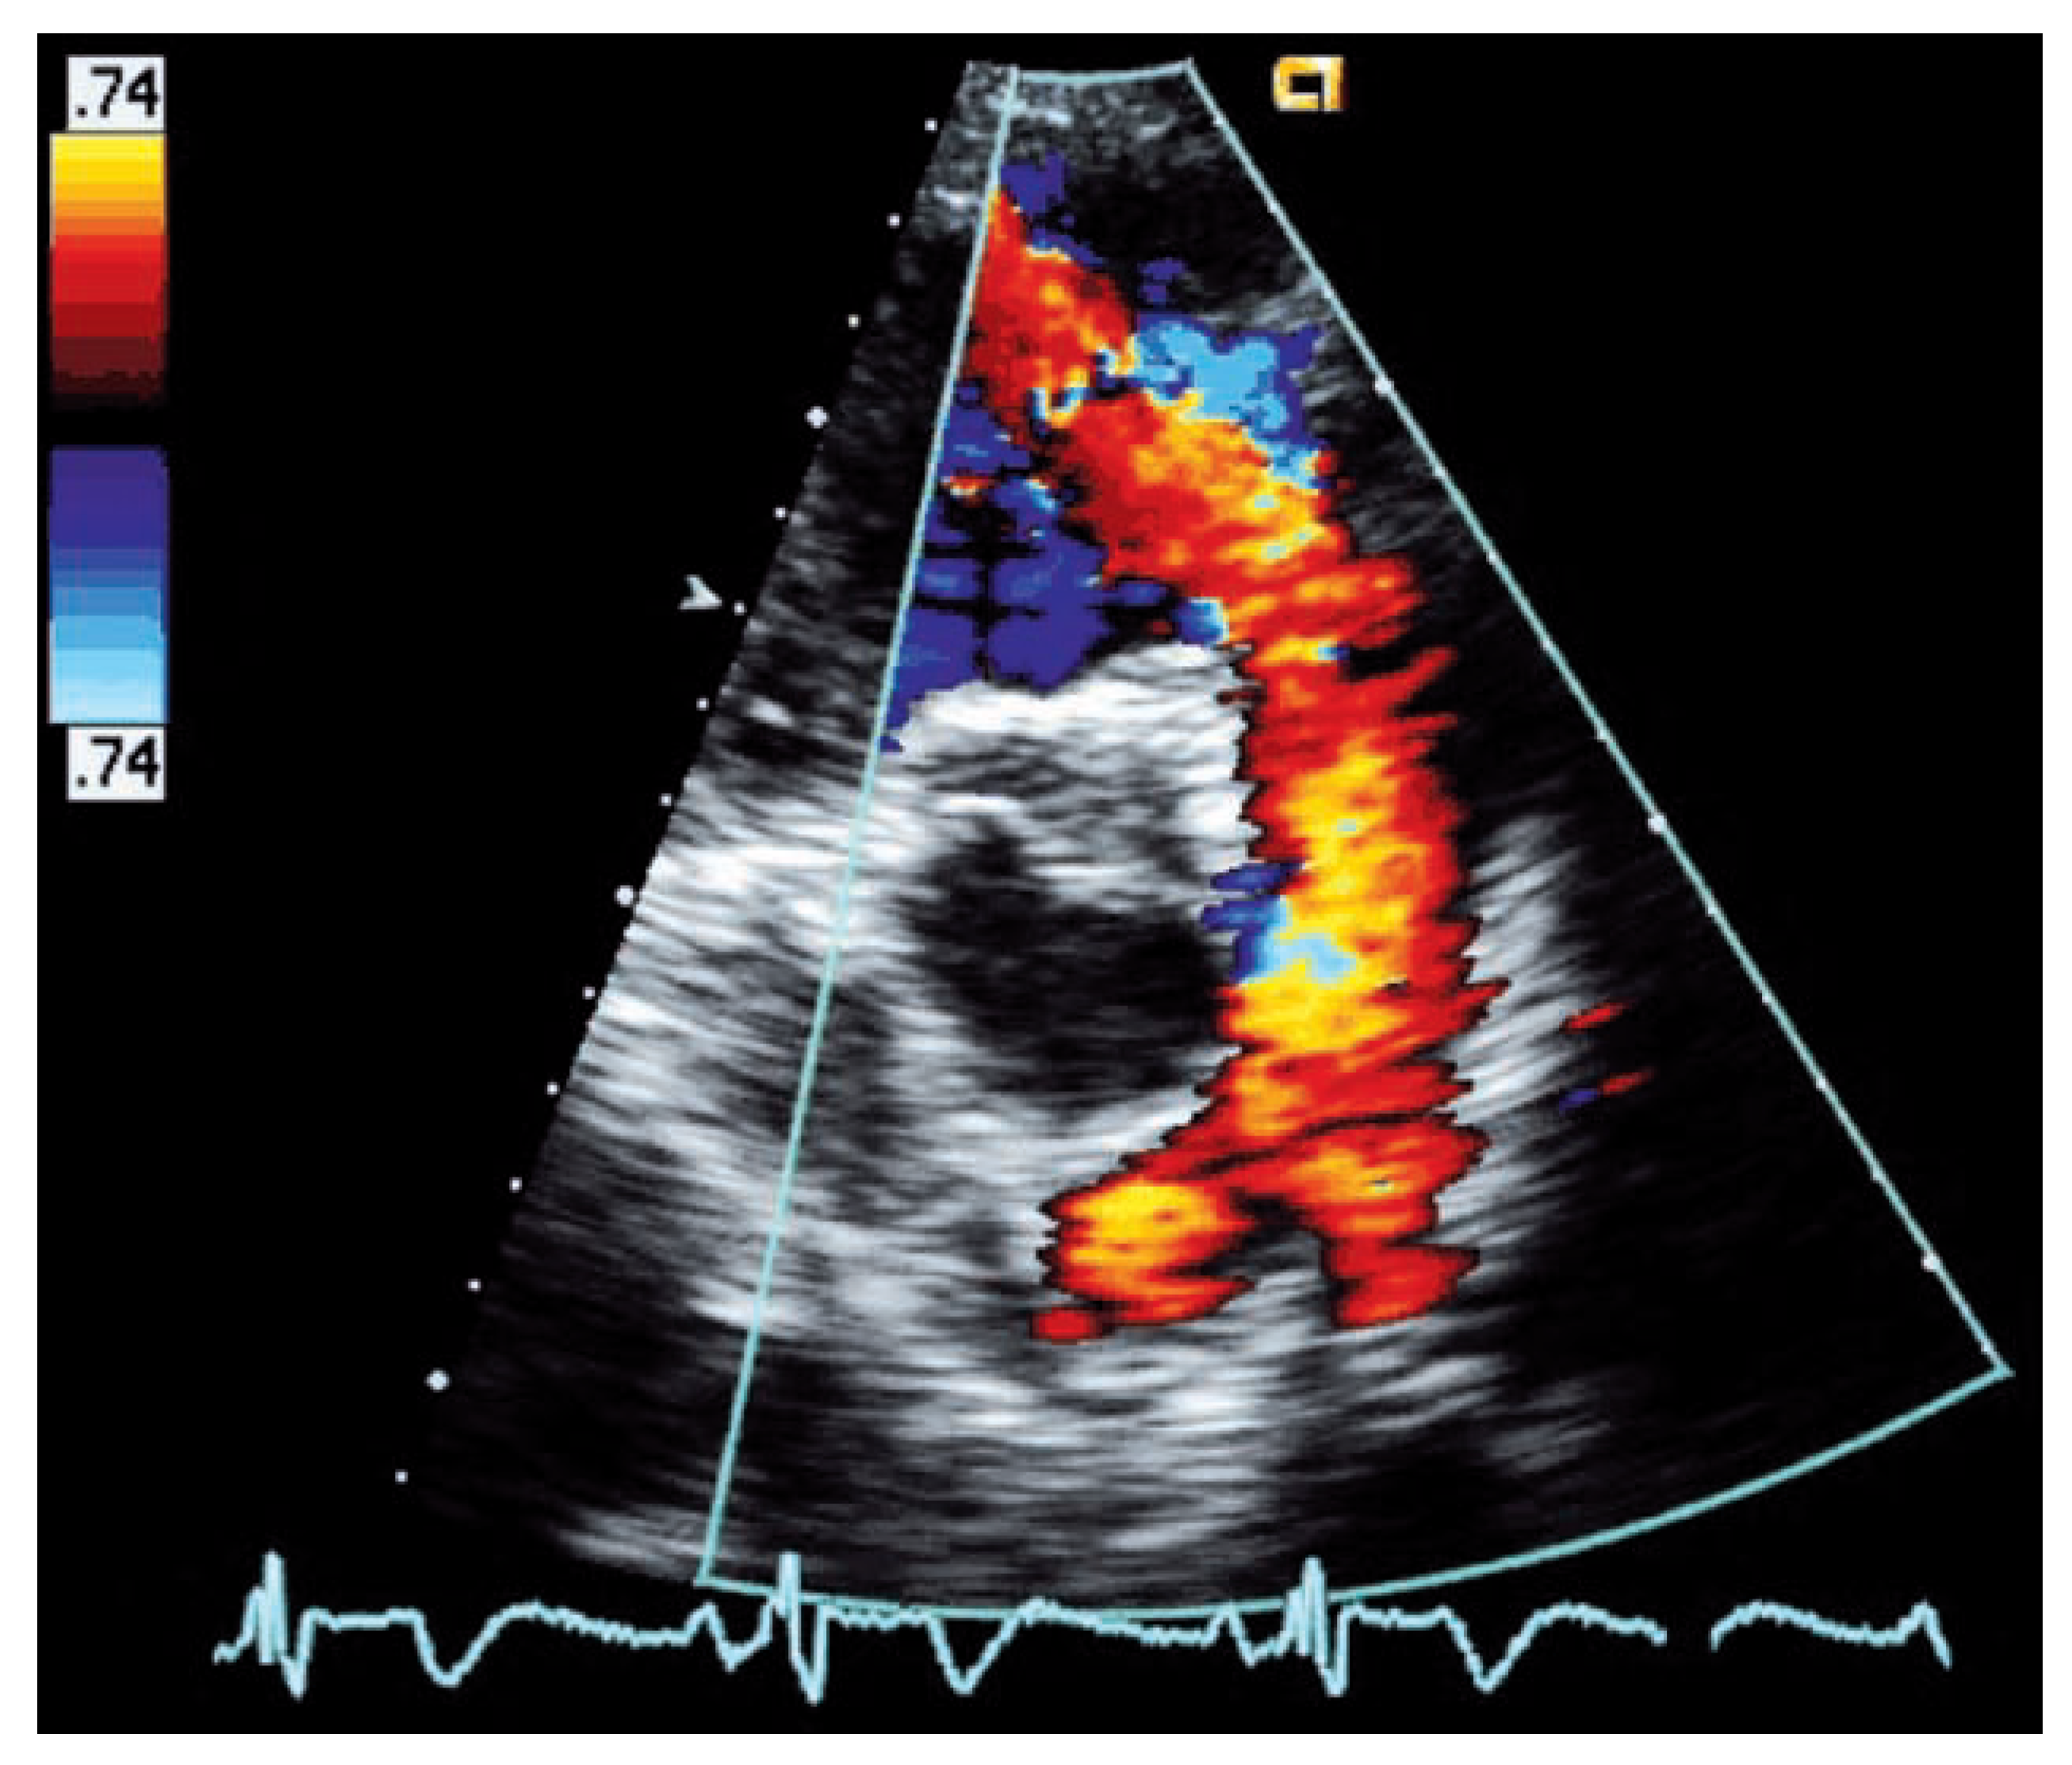

Am häufigsten führt beim adulten Fallot-Patienten eine schwere Pulmonalinsuffizienz bei transanulärem Patch oder ausgiebiger Valvulotomie zu Problemen. Der Schweregrad der Pulmonal-insuffizienz wird aufgrund des tiefen diastolischen Druckgradienten zwischen Pulmonalis-Hauptstamm und rechtem Ventrikel echo-kardiographisch oft unterschätzt, da je nach Grösse der Regurgitationsöffnung ein beinahe laminares Regurgitations-Flussprofil auftreten kann (

Abb. 5). Hinweise für eine schwere Pulmonalinsuffizienz sind, nebst dem laminaren retrograden Flussprofil, eine kurze Pressure-Halftime (<100 ms) [

21] im Doppler-Si-gnal und damit verbunden eine kurze Dauer des diastolischen Rückfluss-Signales bezogen auf die diastolische Füllungszeit (Pulmonary Regurgitant Index <0,77) [

22]. Ein Regurgitationssignal im CW-Doppler, das eine vergleichbare Signalintensität wie der systolische Vorwärtsfluss aufweist, ist ein weiterer Hinweis für ein beträchtliches Regurgitationsvolumen. Die kurze Dauer des diastolischen Rückflusses einer schweren Pulmonalinsuffizienz führt in der Auskultation zu einem kurzen Decrescendo-Diastolikum, das ab und zu den Kliniker fälschlicherweise zur Annahme verleiten lässt, das Regurgitationsvolumen sei unbedeutend. Zur Quantifizierung des Regurgitationsvolumens sowie der zuverlässigen Bestimmung der RV-Volumina wird je länger je mehr das kardiale MRI eingesetzt.